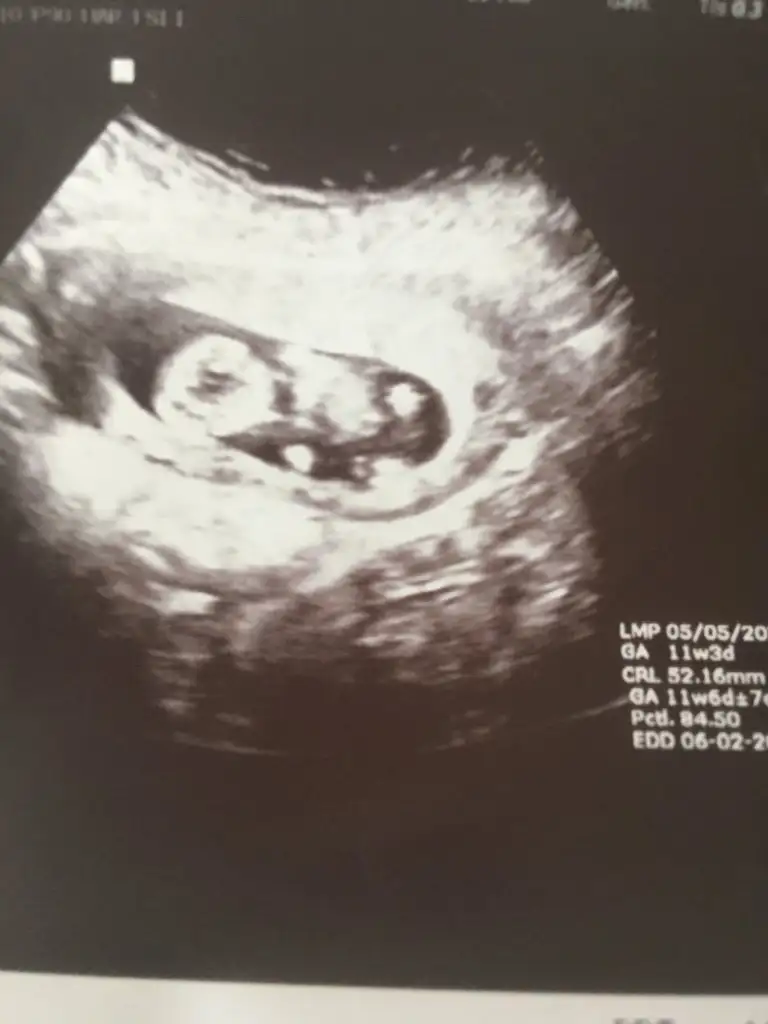

Kız gibi sanki emin olamadımEki Görüntüle 2892053 Eki Görüntüle 2892054 @Ikra meyra acaba müsait olunca bakar mısın? 11+6 oldu belli olur mu biraz?

Teşekkür ederimKız gibi sanki emin olamadım

Bugün cinsiyetini öğrendik,kızımız olacak. Teşekkürler zaman ayırdığınız için.Erkek gibi sanki

Sağlıkla gelsin prensesBugün cinsiyetini öğrendik,kızımız olacak. Teşekkürler zaman ayırdığınız için.![]()